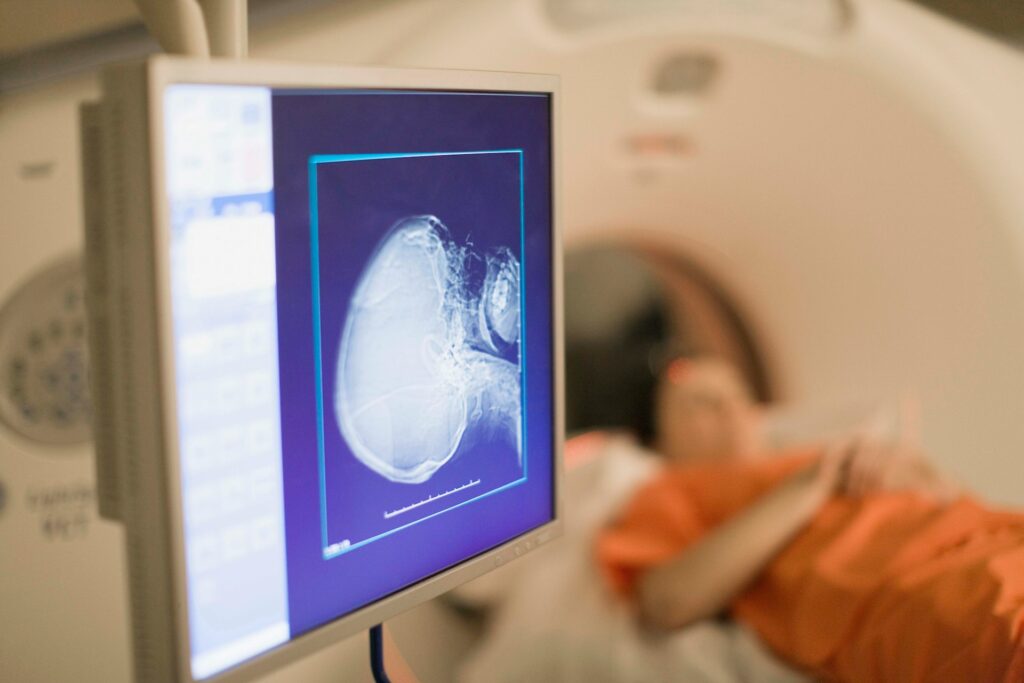

Die Gelenke sind das Herzstück unserer Beweglichkeit, und gerade im Alter spielen sie eine zentrale Rolle für unser Wohlbefinden und unsere Unabhängigkeit. Doch mit den Jahren nehmen Abnutzungen und Verschleißerscheinungen zu, was das Risiko für Erkrankungen wie Arthrose oder andere degenerative Gelenkveränderungen deutlich erhöht. Genau hier setzt die Prävention an: Durch frühzeitige Untersuchungen und gezielte Maßnahmen können viele Beschwerden verhindert oder zumindest gelindert werden. Ein MRT als Vorsorge für die Gelenke im Alter kann dabei eine wichtige Rolle spielen, da es frühzeitig Veränderungen im Gelenk aufzeigen kann.

- Bildgebende Verfahren wie ein MRT, das detaillierte Einblicke in den Zustand des Gelenks bietet

Das MRT als Vorsorge für die Gelenke im Alter ist besonders wertvoll, da es nicht nur Knochen, sondern auch Knorpel, Bänder und Weichteile abbilden kann. Durch diese detaillierte Darstellung lassen sich bereits kleinste Veränderungen erkennen, bevor sie zu ernsthaften Problemen führen.

Ein MRT ist eines der präzisesten diagnostischen Werkzeuge zur Untersuchung der Gelenke. Es nutzt magnetische Felder und Radiowellen, um detaillierte Bilder von Knochen, Knorpeln und Weichteilen zu erstellen, die mit anderen bildgebenden Verfahren oft nicht erfasst werden können. Für Menschen, die im Alter vermehrt unter unklaren Gelenkschmerzen leiden, ist das MRT eine wichtige Methode, um die Ursachen herauszufinden und die richtige Behandlung zu beginnen.

Die Anwendung eines MRTs in der Vorsorge erlaubt es, Probleme wie Knorpelverschleiß, Entzündungen oder andere pathologische Veränderungen im Gelenk frühzeitig zu erkennen. Besonders hilfreich ist es bei Patienten, die bereits erste Anzeichen von Arthrose zeigen oder eine genetische Veranlagung für Gelenkerkrankungen haben. Ein regelmäßiges MRT der Gelenke kann somit helfen, den Verlauf der Erkrankung zu überwachen und entsprechend anzupassen.

Die Vorsorge für die Gelenke im Alter sollte ein integraler Bestandteil der Gesundheitsstrategie jedes Menschen sein. Durch regelmäßige Untersuchungen, lassen sich mögliche Schäden frühzeitig erkennen und behandeln. Dies trägt dazu bei, die Lebensqualität zu erhalten und die Mobilität auch im fortgeschrittenen Alter zu sichern. MRT als Vorsorge für die Gelenke im Alter ist eine der effektivsten Methoden, um Gelenkprobleme rechtzeitig zu diagnostizieren und gezielte Maßnahmen zu ergreifen.